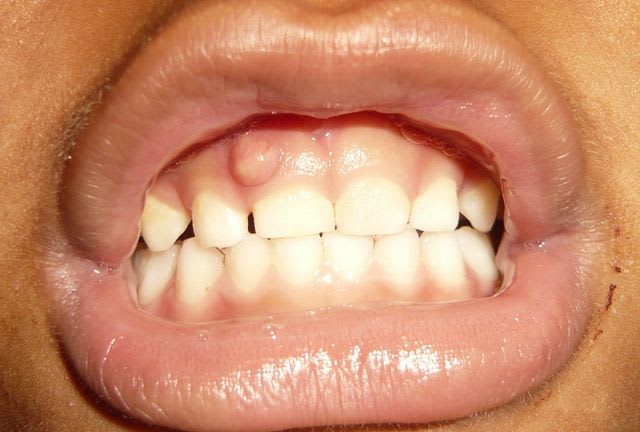

Voici un cas clinique de pédodontie:

Enfant de 4 ans et 7 mois.

Découverte fortuite lors du brossage par ses parents. Pas de douleurs signalées par l'enfant. Pas de souvenir de traumatisme pas de témoins mais l'enfant est un peu "cascadeur". Enfant en bonne santé générale.

Sur la radio, on observe une image de résorption latérale.

Pas de douleurs à la palpation ou au contact dentaire de la 51. Mobilité peut être un peu supérieure à la mobilité physiologique entre le pouce et l'index mais difficile a évaluer.

Quel est votre diagnostic? Quel traitement mettriez vous en place? quel est votre pronostic?